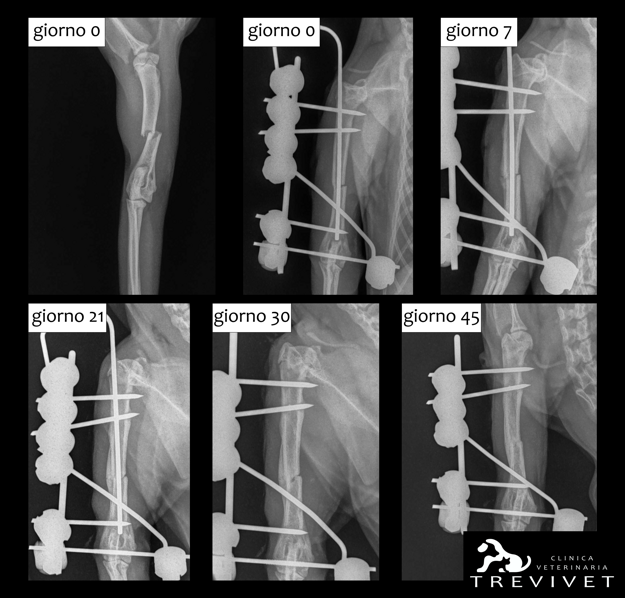

In accordo coi proprietari si decide di effettuare una riduzione chirurgica della frattura, con stabilizzazione del segmento osseo attraverso l’utilizzo di un fissatore esterno TIE-IN mono-planare bi-laterale (tipo IIA) formato da chiodi di Kirshner filettati, collegati a un barra in acciaio con morsetti Mainard e viene aggiunta una barra antirotazionale.

Vengono effettuati controlli regolari a distanza di 10-15 giorni per valutare la stabilità dell’impianto e il proseguo della guarigione ossea.

A distanza di 4 settimane dall’intervento si decide di alleggerire l’impianto, per spostare parte delle forze di carico sul callo osseo in formazione e favorirne la “maturazione”.

Dopo altre 2 settimane il callo osseo viene giudicato adeguatamente solido e si procede alla rimozione dell’impianto, si consiglia di mantenere Favy per altre 2 settimane a riposo.